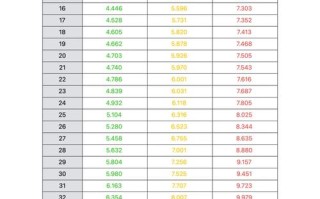

- 囊肿本身:大小、位置、是否与脑室相通。

- 周围结构:是否对脑组织、脑室系统造成压迫,导致脑积水(脑脊液循环不畅)。

- 宝宝的整体状况:测量头围,评估神经发育情况。